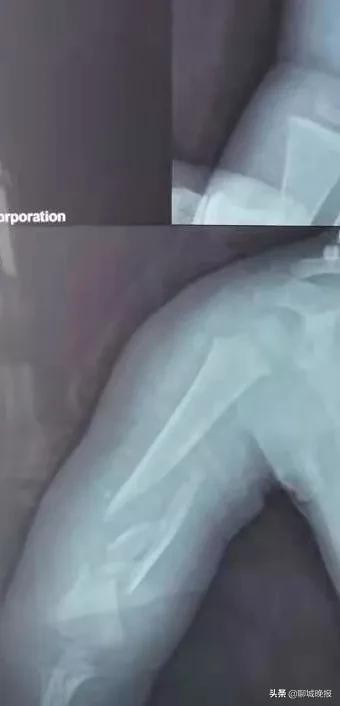

原来,3月4日下午,患儿在玩耍时看到转动的机器,非常好奇,趁大人一个不留意便伸手摸了上去,结果被绞伤导致右臂粉碎性骨折,遂来我院就医,诊断为右肱骨干粉碎性骨折,右尺桡骨骨折,右第2、3、5掌骨骨折。

术前 ↑ 术后 ↓ 对比